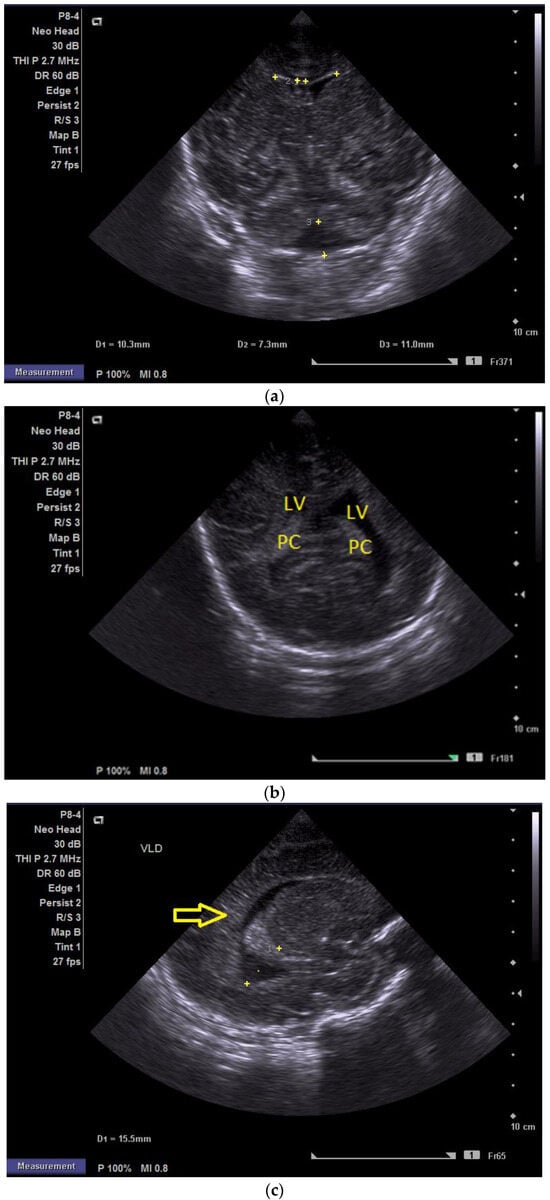

At two minutes of life, with a heart rate of 120 bpm, chest compressions were discontinued, and the patient continued to be ventilated via endotracheal tube. The newborn was then transported while ventilated in an incubator to the neonatal intensive care unit (NICU), where SIMV ventilation was initiated, along with surfactant administration. The day one cranial ultrasound (CUS) showed bilateral periventricular hyperechoic images and enlargement of the lateral ventricles (Figure 1a–d).

(a) Cranial ultrasound. Day one. Coronal view. D1 and D2—Levine index measurement. D3—cisterna magna measurement (personal image collection). (b) Cranial ultrasound. Day one. Coronal view. Lateral ventricle dilatation. LV—lateral ventricles. PC—plexus choroidus (personal image collection). (c) Cranial ultrasound. Day one. Right lateral ventricle. D1—thalamo-occipital distance measurement. Yellow arrow—parieto-occipital hyperechoic images (personal image collection). (d) Cranial ultrasound. Day one. Left lateral ventricle. D1—thalamo-occipital distance measurement. Yellow arrow—parieto-occipital hyperechoic images (personal image collection). (e) Day three. Cranial ultrasound. Coronal view. Ventricular asymmetry. D1 and D2—Levine index measurement. D3 and D4—anterior horn width measurement. Left ventricular enlargement (personal image collection). (f) Day three. Cranial ultrasound. Coronal view. Ventricular asymmetry (left ventricle larger than right ventricle). Yellow arrows—periventricular hyperechoic images are becoming more visible (personal image collection). (g) Day three. Cranial ultrasound. Coronal view. Linear probe. Ventricular asymmetry (left ventricle larger than right ventricle). LV—lateral ventricle (anterior horns). IHF—interhemispheric fissure. Yellow arrows—hyperechoic images in the thalamic-caudate groove (suggestive of a germinal matrix hemorrhage) (personal image collection). (h,i) Day 13. First LP. Cranial ultrasound. Coronal view. Up (before LP). D1 and D2—Levine index measurement. LV—lateral ventricles (anterior horns). IHF—interhemispheric fissure. Down (after LP). Dimensions of ventricles were reduced after LP. D1 and D2—anterior horn width. LV—lateral ventricles (anterior horns). OH—occipital horn (personal image collection). (j,k) Day 19. Second LP. Cranial ultrasound. Coronal view. Dimensions of ventricles were reduced after LP. Left (before LP). D1 and D2—Levine index measurement. Right (after LP). D1 and D2—Levine index measurement (personal image collection). (l) Day 39. Cranial ultrasound. Coronal view. Yellow arrows—periventricular cystic hyperechoic images—suggesting periventricular leukomalacia (cystic form) (personal image collection). (m) Head circumference-for-age. “X” symbols represent the measurements performed from birth and follow-up examinations. Initially, the head circumference was under the curve (personal image collection) [28].

After 72 h, the patient was extubated. The CUS showed bilateral IVH (grade III Volpe/Papile) (Figure 1e,f).

During the in-stay, two lumbar punctures (LP) were performed (Figure 1h–k).

In evolution, our patient presented bilateral ventricular dilatation and bilateral PVL (cystic form, grade III) (Figure 1l). The neurological assessment established eye contact and the infant could hold its head during the traction maneuver. The passive tone assessment showed the “scarf sign”, with the elbow at the midline bilaterally and a popliteal angle of 90°. The deep tendon reflexes (DTRs) were symmetrical.